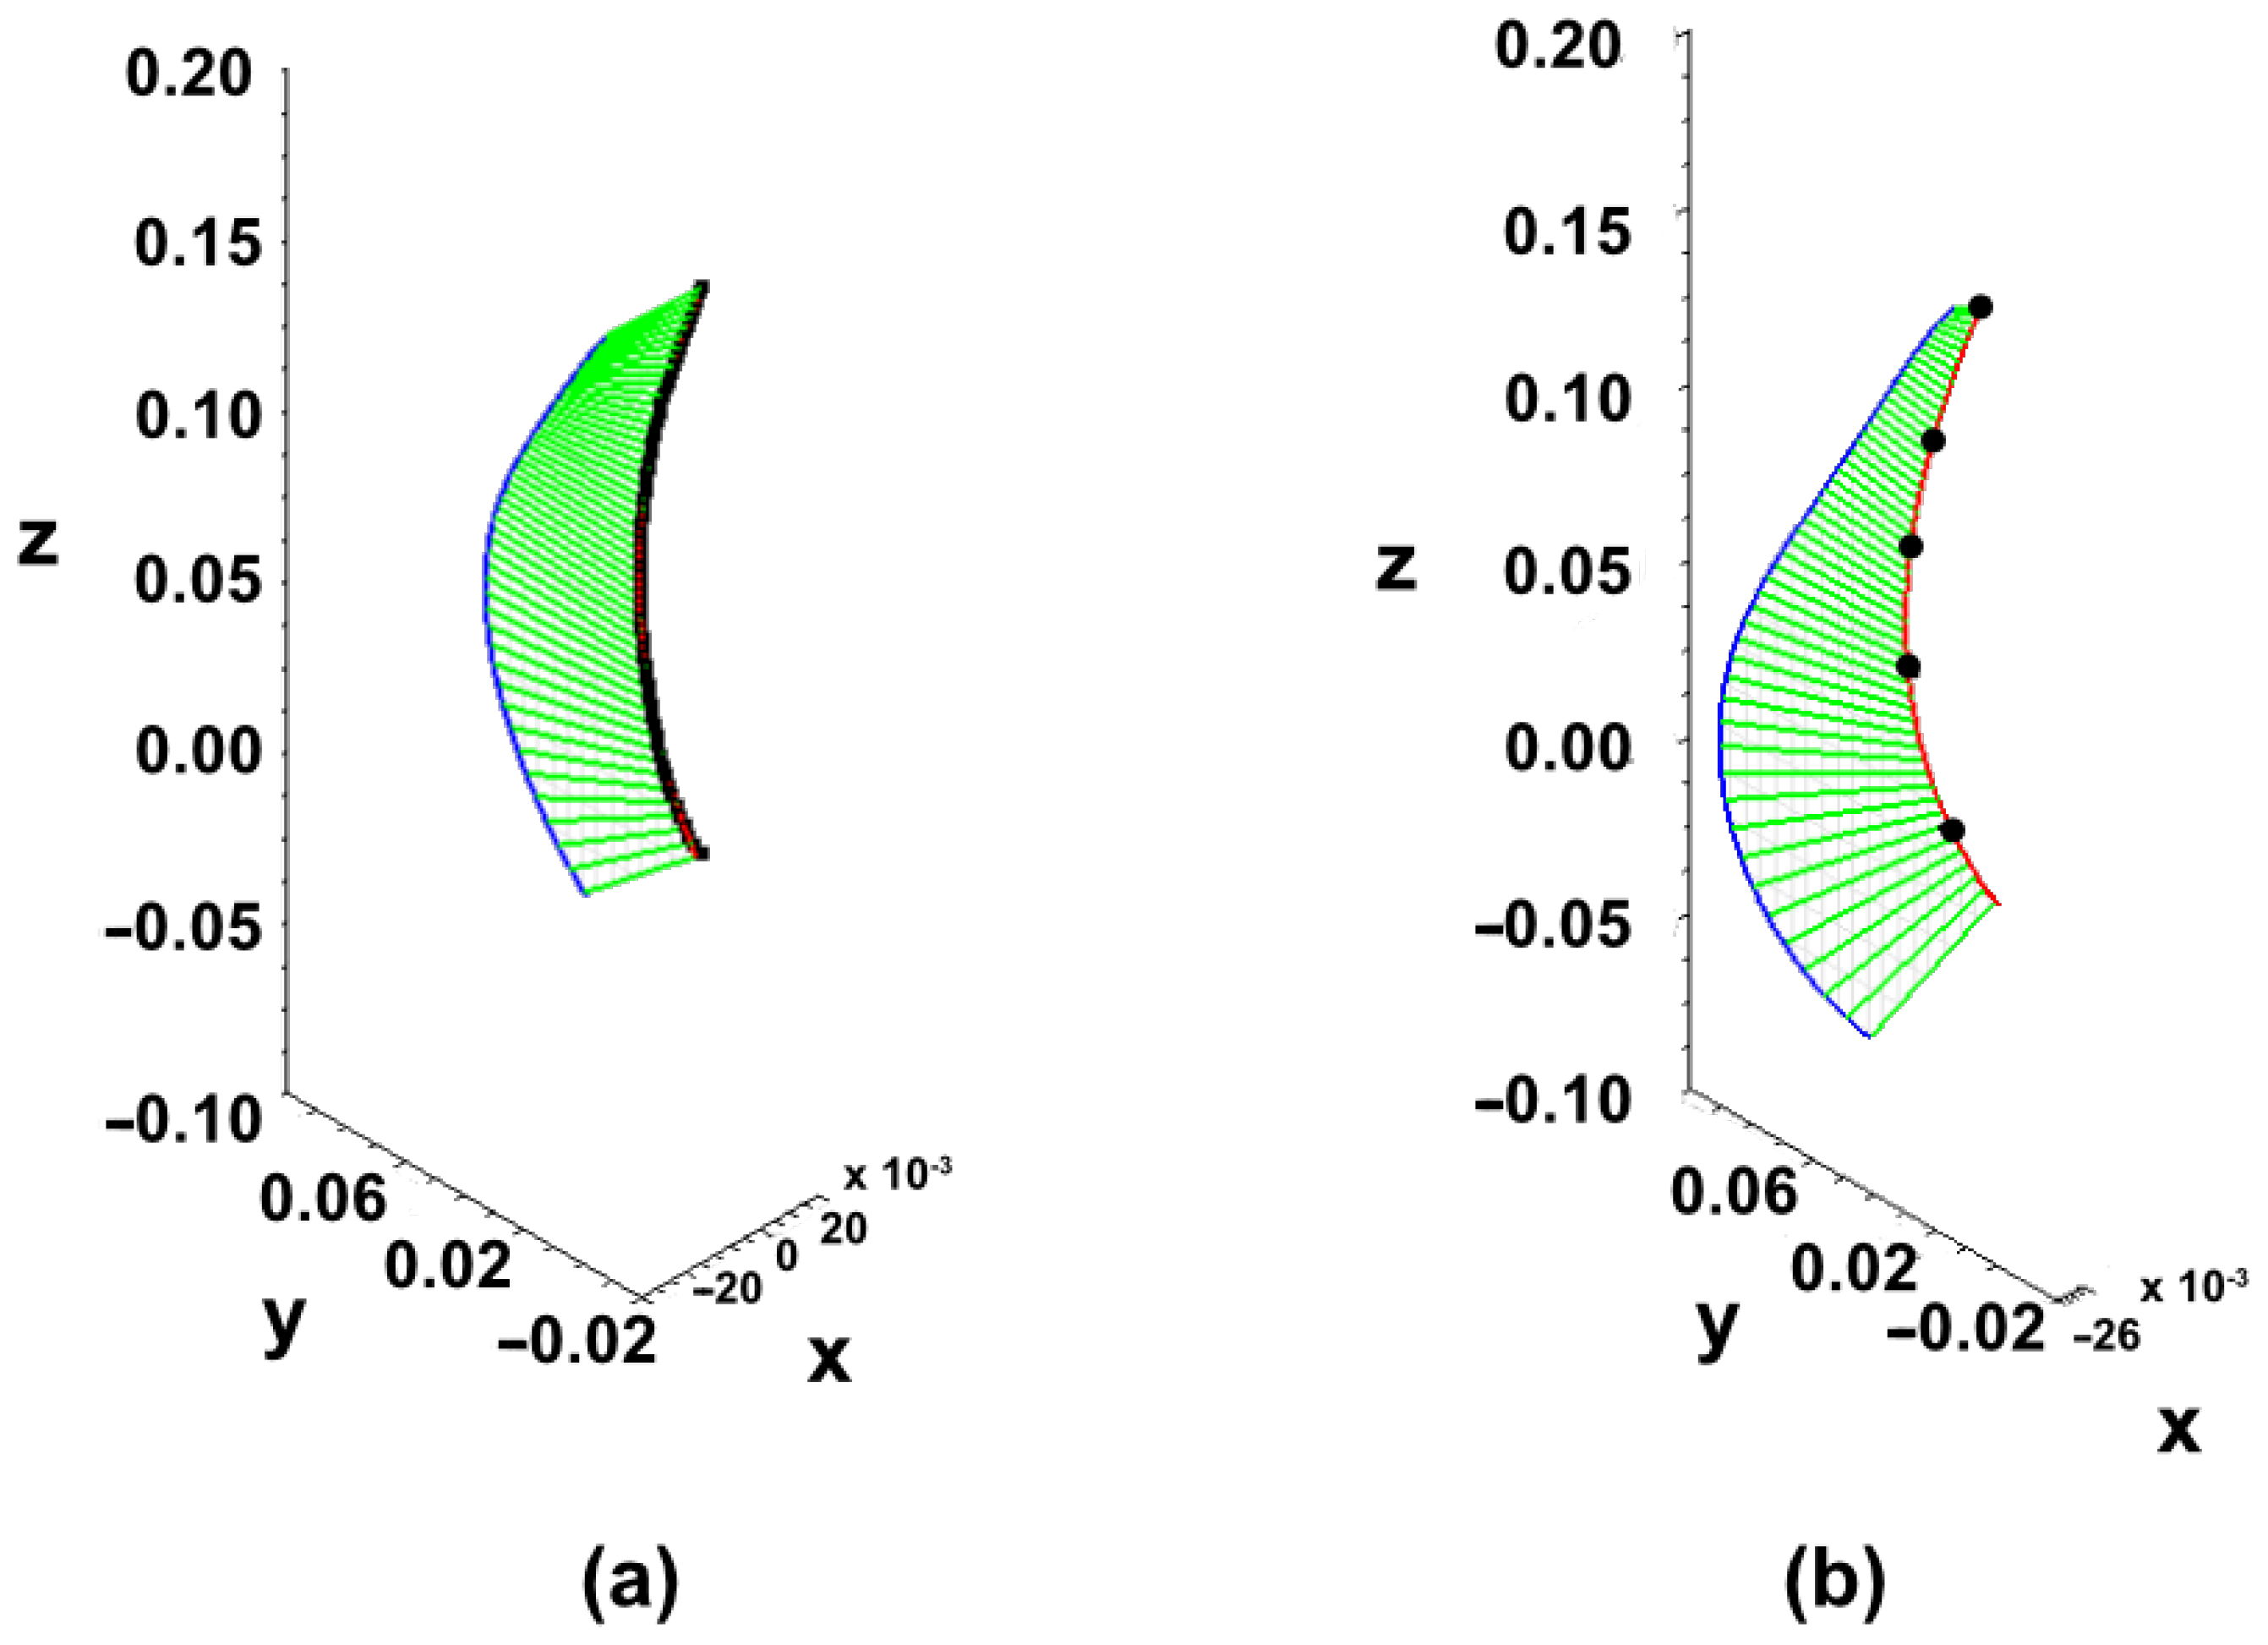

3.2. Creation of New Lordosis Model from 3D Curvature